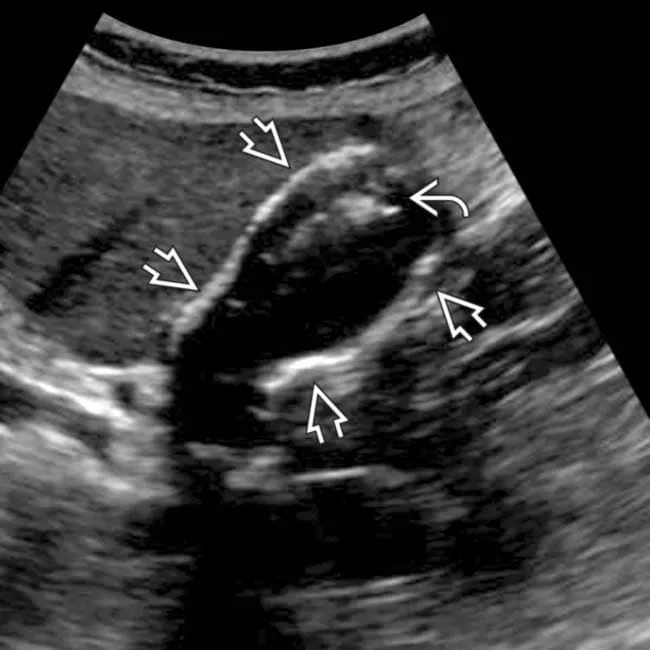

초음파에서 담낭 용종은 벽에 고정되어 움직이지 않고 후방 음영이 없는 돌기 형태,

반면 담낭 결석은 체위 변화에 따라 이동하며 강한 반사와 그림자(후방 음영)를 보입니다.